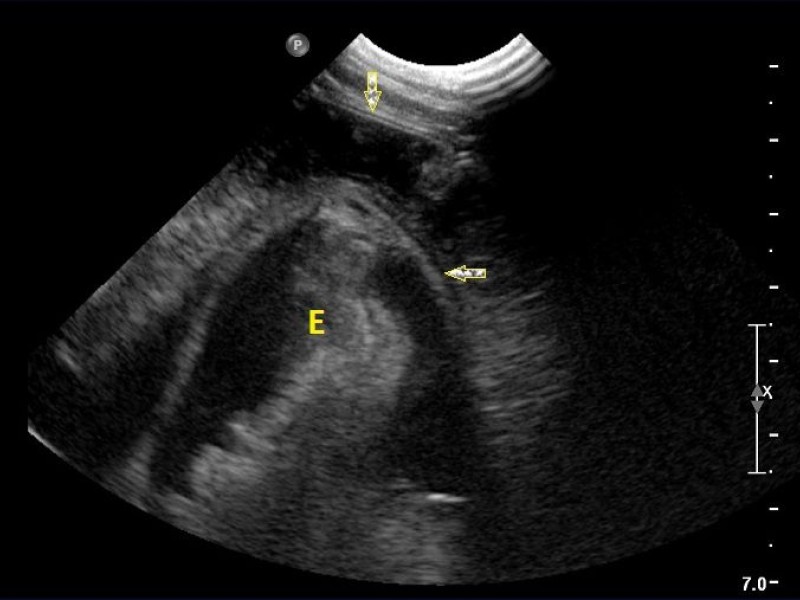

A thoracic ultrasound was performed and allowed the visualization of an intestinal structure within another intestinal structure thanks to the recognition of the 5 layers (arrow). The stomach is depicted by the letter "E".